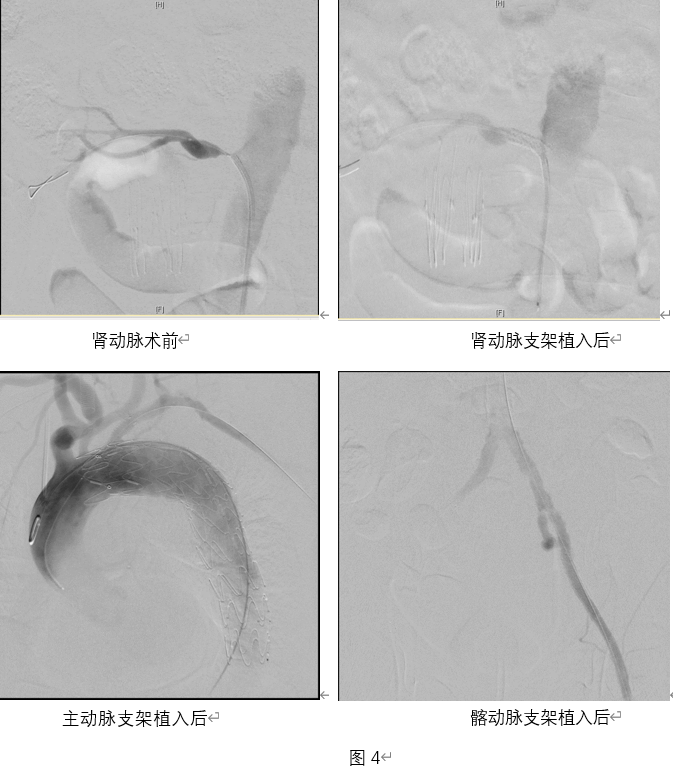

术前CTA检查提示,该患者全身动脉血管多处病变(图1),其中左侧髂动脉严重钙化狭窄(图2),不仅是患者左下肢跛行的“元凶”,也会成为主动脉瘤微创介入治疗的“拦路虎”,如此坚硬的钙化病变,手术操作风险高、难度大。经手术团队反复研判,决定引入国际先进的Shockwave外周血管内冲击波治疗技术,该技术通过脉冲发放血管内冲击波,“隔山打牛”般作用于钙化病变,使得斑块重塑,血流恢复通畅、血管恢复柔顺,能够最大限度恢复血管正常生理功能。

术中,通过细腻的导丝、导管操作,手术团队率先在左侧髂动脉打通一丝通道,通过血管造影,评估髂动脉及左下肢血流全貌;结合术前CTA检查,于髂动脉严重钙化狭窄部位通过Shockwave血管内冲击波导管,共发放6组血管内冲击波,短短几分钟,髂动脉血流完全恢复通畅,血管恢复柔顺,安全、有效、迅速地解决了下肢缺血的问题。